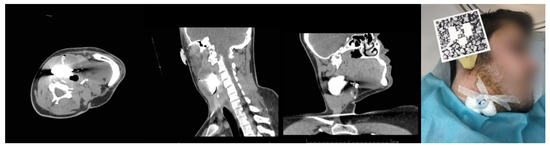

3.2. Case 2. Adjustable Navigation Frame

Operating Principle and Conclusion